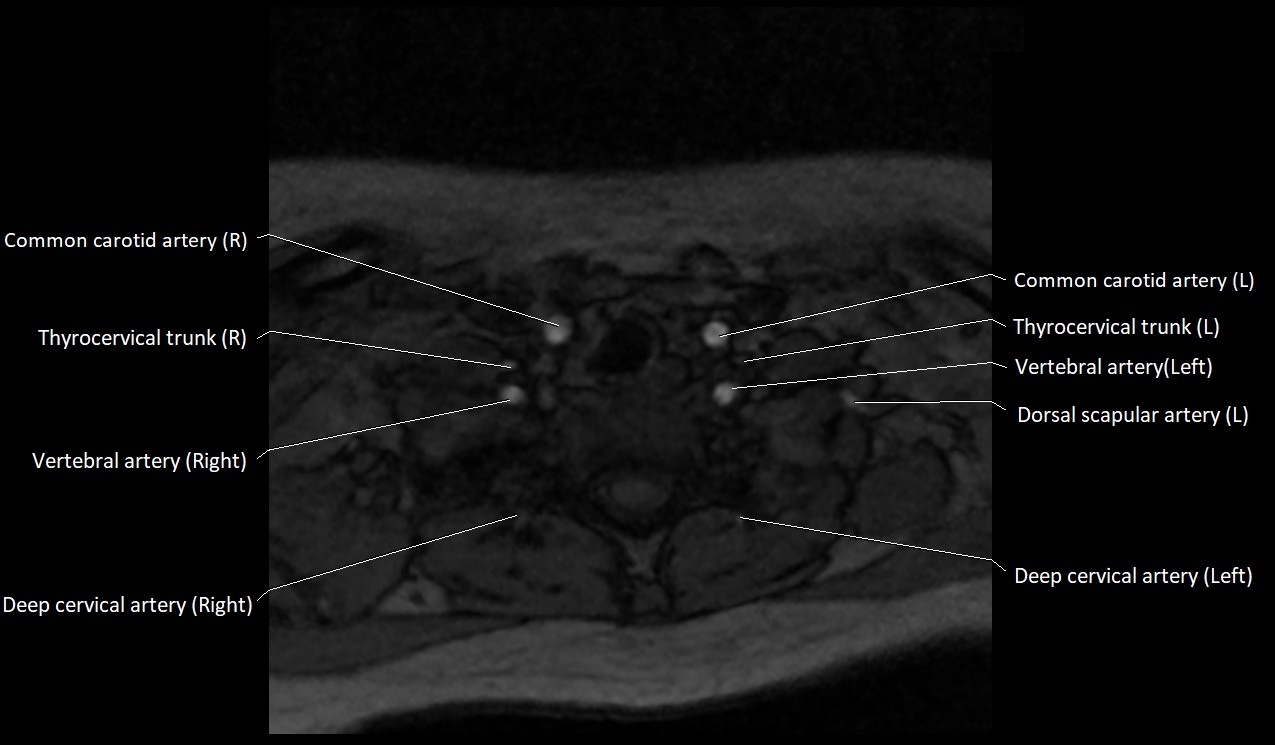

MRI images

image